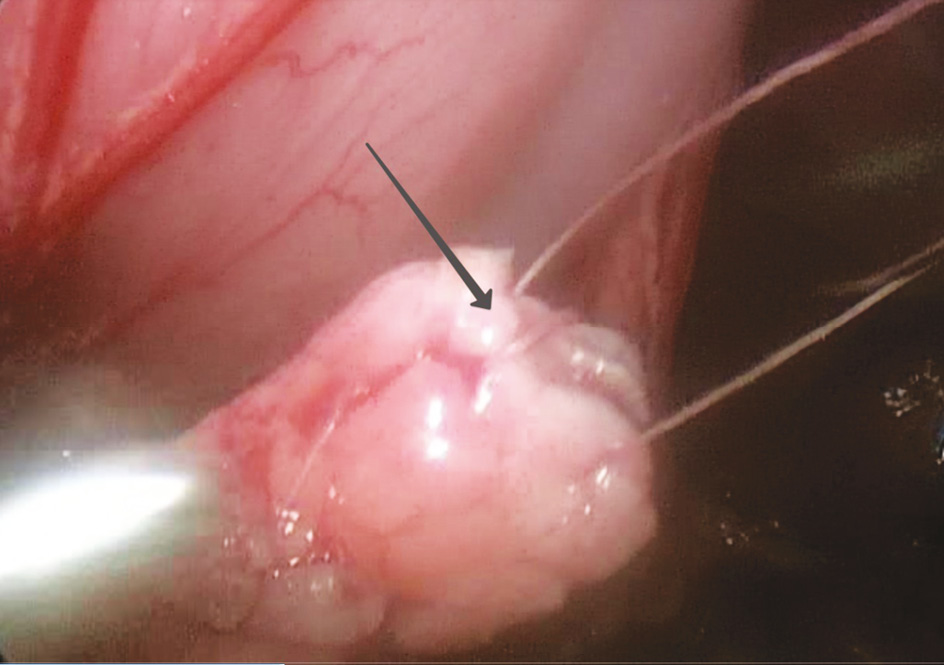

При дальнейшем визуальном осмотре был выявлен округлый участок плотной ткани размерами 0,5 × 0,7 см в головке поджелудочной железы (рис. 6).

Рис. 6. Очаг в головке поджелудочной железы

Fig. 6. Focus in the head of the pancreas

Учитывая «отграниченность» очага от основной ткани, путем монополярной коагуляции выполнена резекция очага патологической ткани (рис. 7) из головки поджелудочной железы также с проведением экспресс-биопсии, подтвердившей отсутствие патологической ткани в краях резекции.

Рис. 7. Резекция очага гиперинсулинизма из головки поджелудочной железы: а — резекция очага патологической ткани; b — участок головки поджелудочной железы после резекции (стрелка указывает на ложе очага)

Fig. 7. Resection of the focus of hyperinsulinism from the head of the pancreas: а — resection of the focus of pathological tissues and b — area of the head of the pancreas after resection (the bed of the focus)